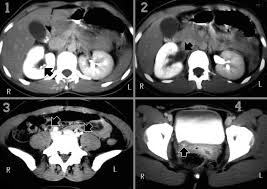

Adenine phosphoribosyltransferase aprt deficiency and 2 8 dihydroxyadeninuria. These are hard deposits of minerals formed in the body s kidneys. Struvite stones a calculus occurring in the renal pelvis with branches extending into the infundibula and calices.

Staghorn calculi more commonly called struvite stones or infection stones are a type of kidney stone.